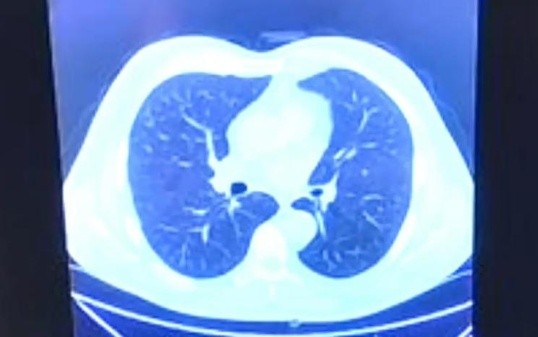

El gobernador de Baja California destacó la importancia de recibir atención médica a tiempo y comentó que deseaba mostrar la rápida evolución del coronavirus mediante imágenes que luego explicó un médico.

"(El coronavirus) afectó mis pulmones de la manera tan voraz y cómo realmente opera, trabaja y destruye el COVID", detalló Bonilla.

"Es para mí importante como gobernador enseñarles, de un pulmón sano, con todos los órganos de mi cuerpo funcionando, cómo un contagio como éste no le importa y te agarra de lo más débil".

Tomografía normal pulmón sano, del jueves 3 de diciembre.